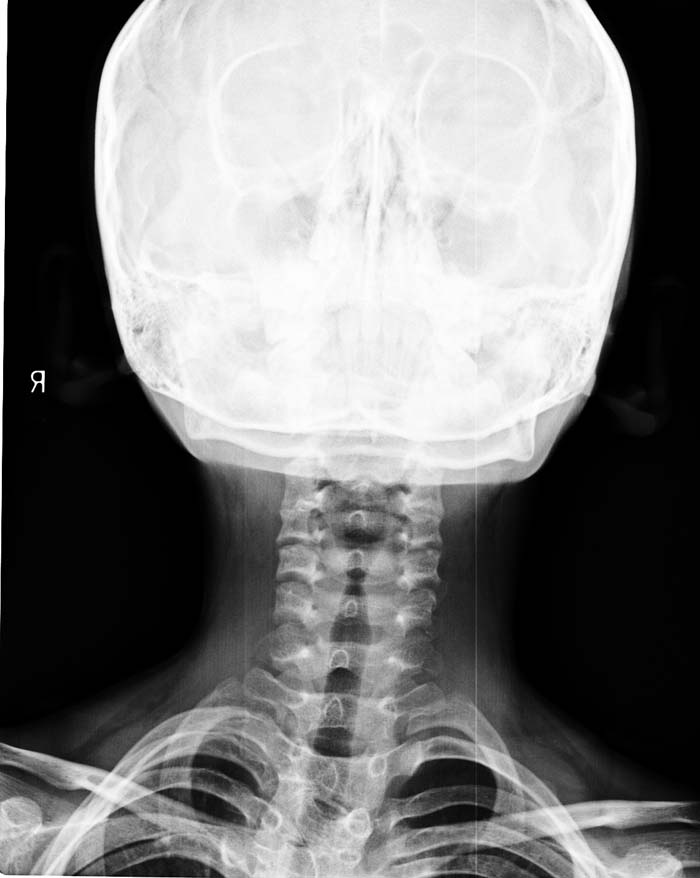

以下是引用zsl6918在2009-10-17 18:51:00的发言:[br]融椎畸形

以下是引用zy_zj在2009-10-17 19:21:00的发言:[br]胸椎8,9椎体融合畸形,伴序列s形弯曲,颈椎稍侧弯,曲度反向。

以下是引用余辉在2009-10-18 10:20:00的发言:[br]支持椎体隔合畸形,肋骨亦有融合,局部椎体密度较低,棘突影像缺如,不排除合并椎体裂,建议ct检查